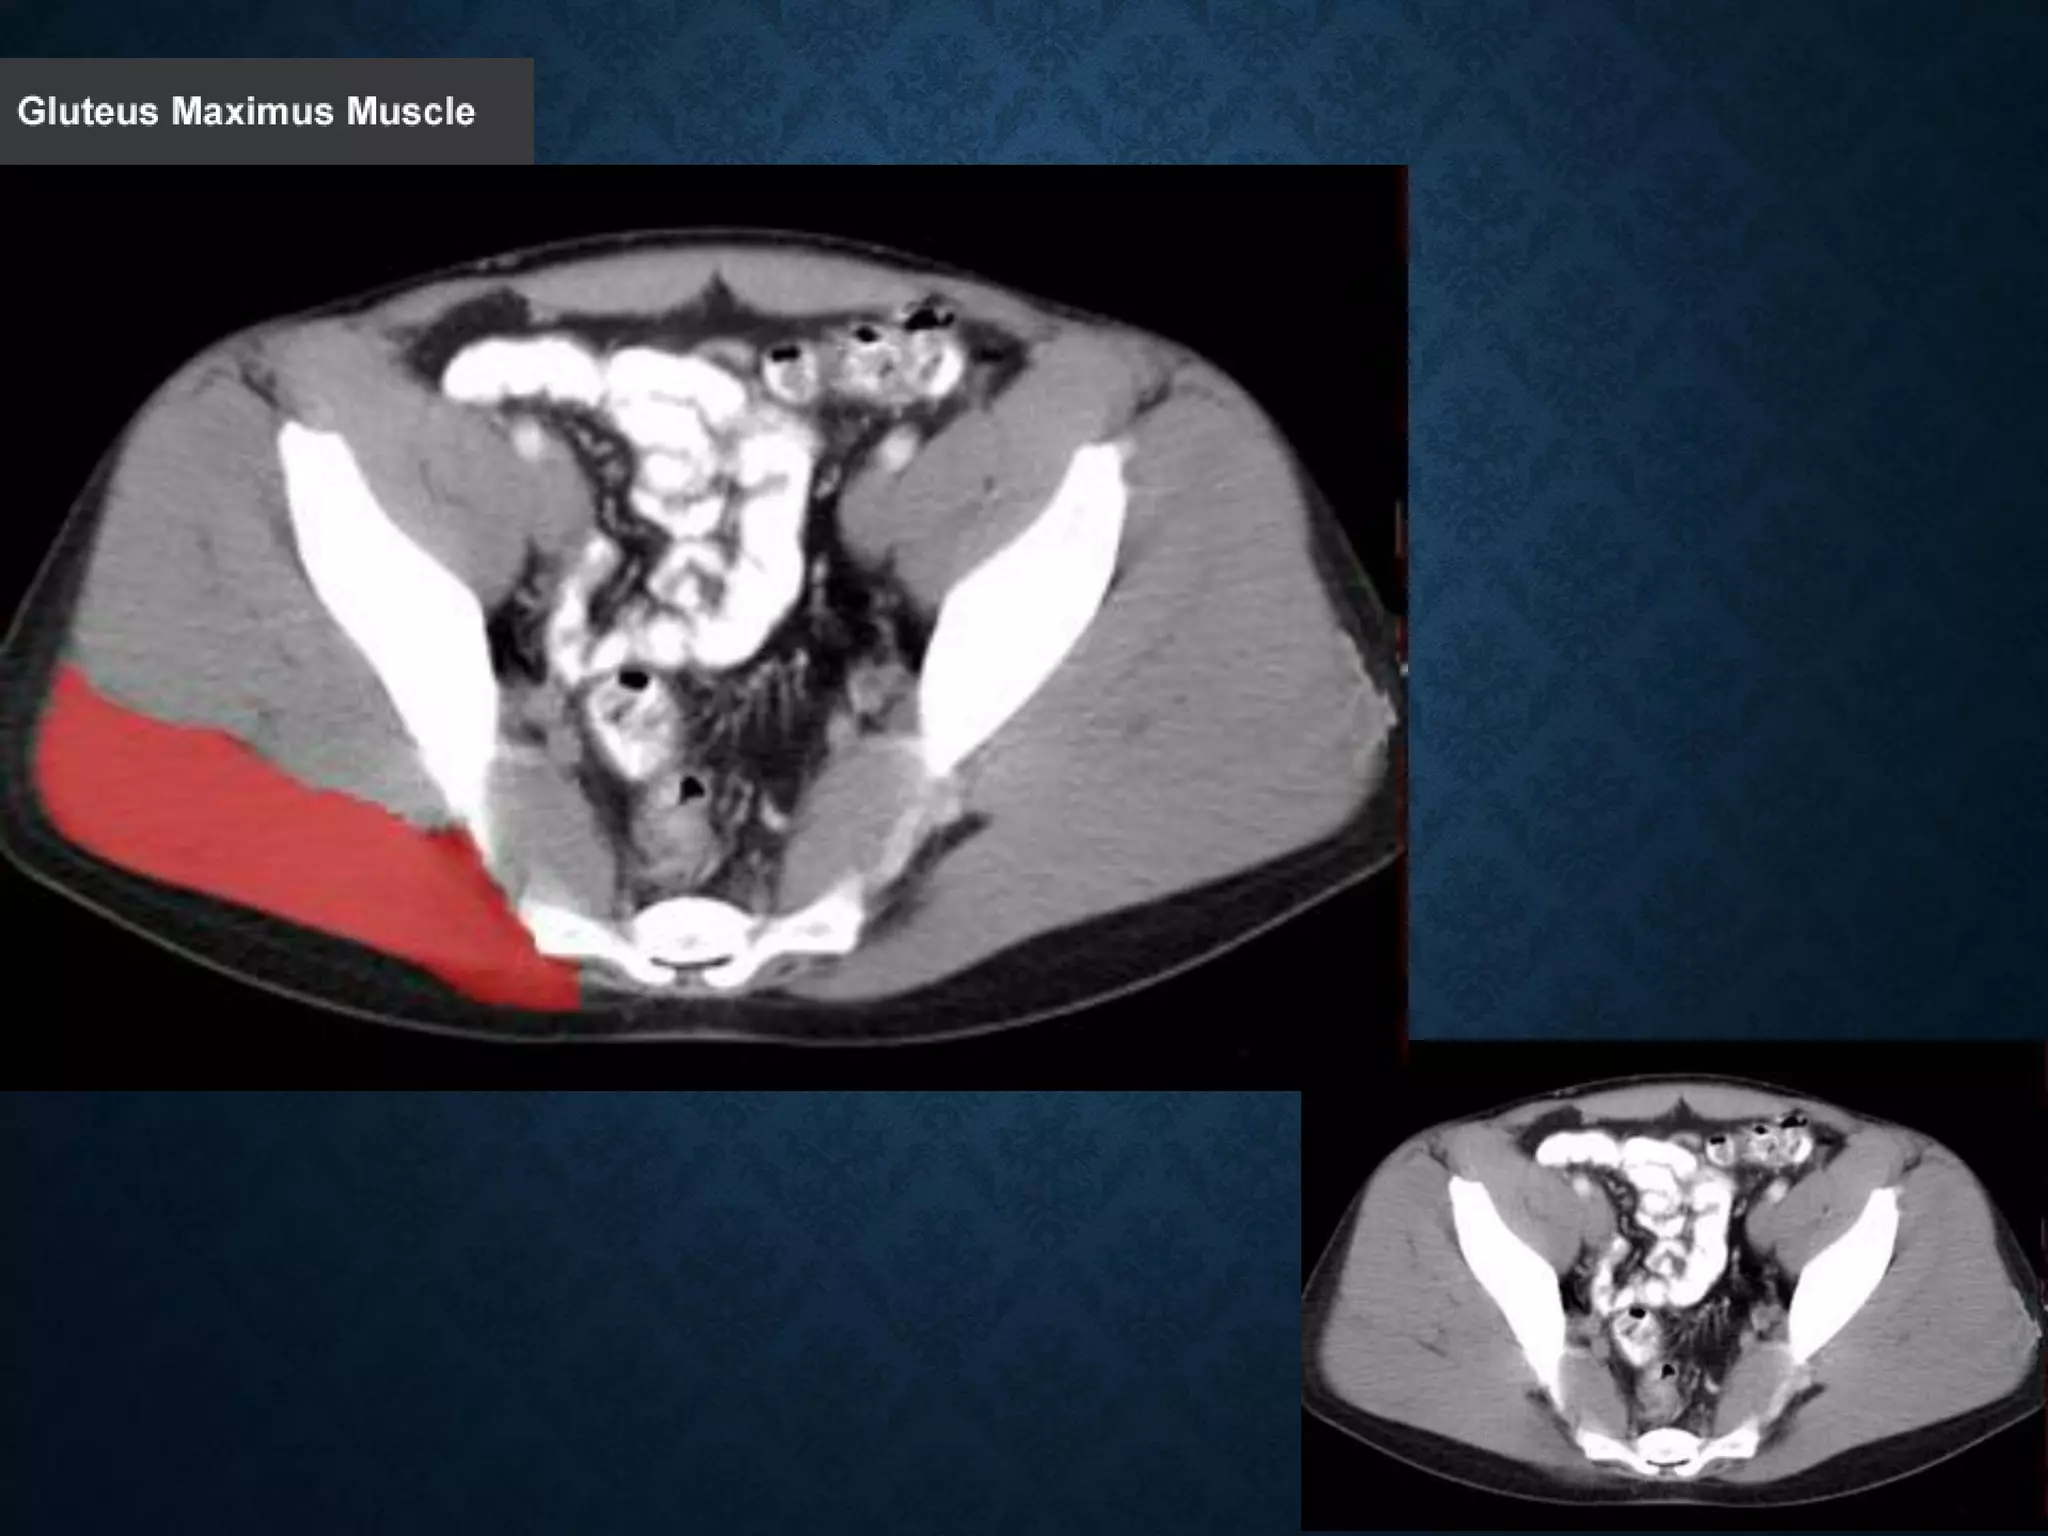

Normal Anatomy- Section 12

Normal Anatomy- Section 13

Normal Anatomy- Section 14 (female)